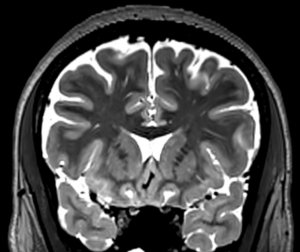

T2

The T2 scan is a 0.9 mm iso 3D T2-space. It is, like the T1, accelerated by a factor of 4, but in this case the scanner allowed 2×2 acceleration, which is both faster and yields better SNR. The scan time for the T2 is 3:10, and the quality is sufficient that a single copy is acquired.

The T2 is collected with no angles. The position parameters from the T1s should be copied for the T2.